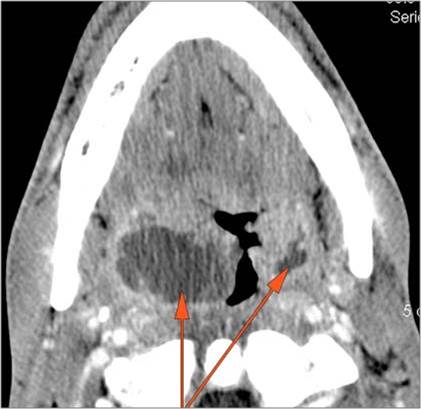

Oropharynx

There is excessive enhancement or thickening of the mucosa or hypertrophy of the palatine or lingual tonsillar tissue or the lymphoid tissue along the glossotonsillar sulci and posterior pharyngeal wall. [Yes/No]

There is abscess relatively centrally within the lymphoid tissue of the palatine tonsil. [Yes/No]

There is abscess at the periphery of the lymphoid tissue of the palatine tonsil within the potential peritonsillar space. [Yes/No]

There is edema within the fat of the adjacent parapharyngeal space. [Yes/No]

There is abscess within the fat of the adjacent parapharyngeal space. [Yes/No]